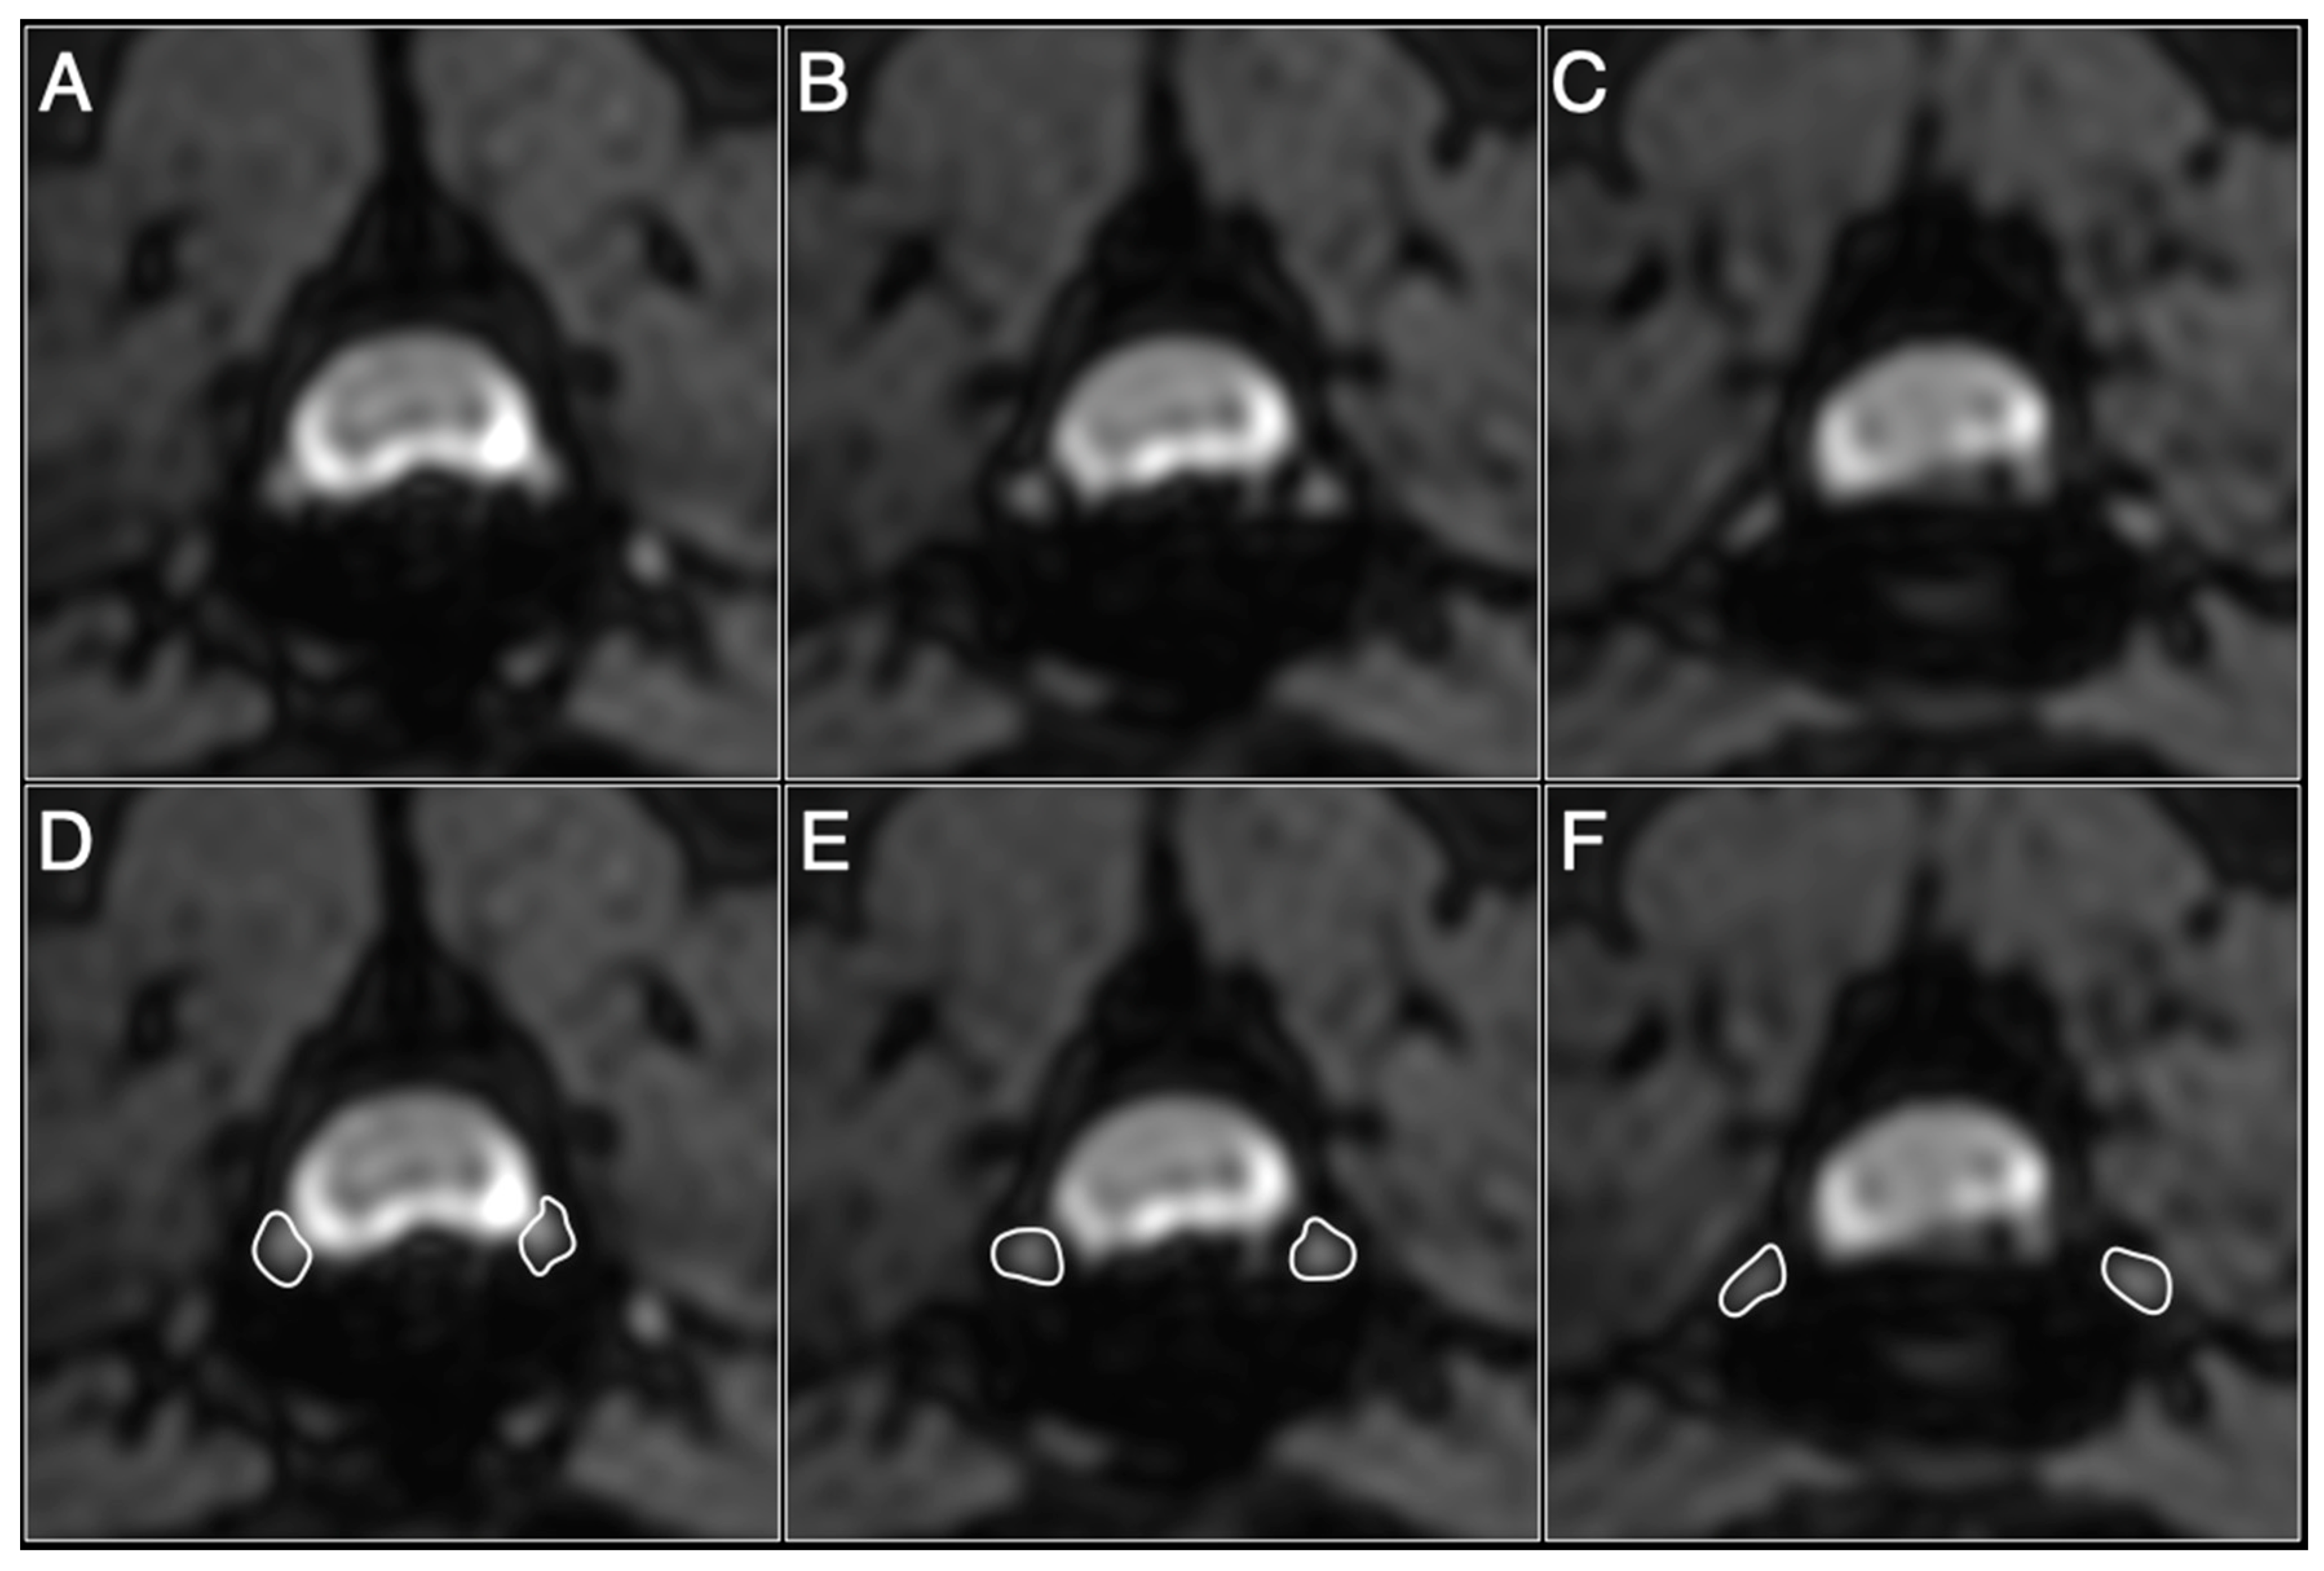

2.3. Image Analysis

3.2. Normalization of the DRG Volumes in Control Dogs